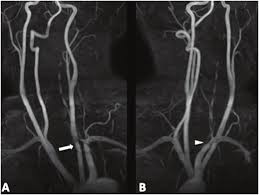

The natural history of cerebrovascular fmd is unknown and management of symptomatic patients can be challenging. A carotid dissection is a tear in the inner layer of the wall of a carotid artery that allows bleeding into the artery wall. Internal carotid artery (ica) dissection, like arterial dissection elsewhere, is a result of blood entering the media through a tear in the intima 1 and is a common cause of stroke in younger patients. Carotid artery dissection has been described after chiropractic manipulation. It can involve a carotid or vertebral artery and sometimes multiple arteries can be involved.

Arterial dissection is a tear of the inside of the artery. The tear that initiates the dissection may occur spontaneously or after injury. Medical imaging tests can help rule out other conditions with similar symptoms. The first portion of each carotid artery is the called the common carotid artery. These arteries supply blood to your brain. May occur spontaneously, or in the setting of major/minor neck trauma (mvc (classically a seat belt injury)) vs. Similarly, dissections affect distal parts of the extracranial vertebral artery, whereas atherosclerosis tends to involve the proximal segments C0338585) spontaneous or traumatic separation of the layers of the carotid artery wall. Carotid dissection is a tear in the carotid artery wall. But it's still a dangerous situation. I will elaborate in a few sentences. Blood vessel walls normally have three layers, and a tear in any of these can allow blood to flow into the resulting space, causing the vessel to bulge. It manifests with headache, neck pain, temporary vision loss, and/or ischemic stroke.